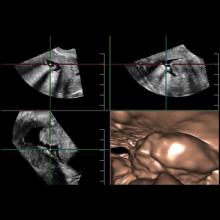

With ever-increasing concerns about radiation dose and the appropriate use of diagnostic imaging tests, doctors are continuously looking for ways to better image their patients. Advances in ultrasound are making the technology appear more attractive for certain clinical applications, from breast health to cardiology, thanks to their noninvasiveness, cost-effectiveness and lack of radiation. Some of the emerging innovations in ultrasound, such as real-time 3-D imaging and the development of wireless transducers, are set to keep the market going throughout 2013 and beyond.